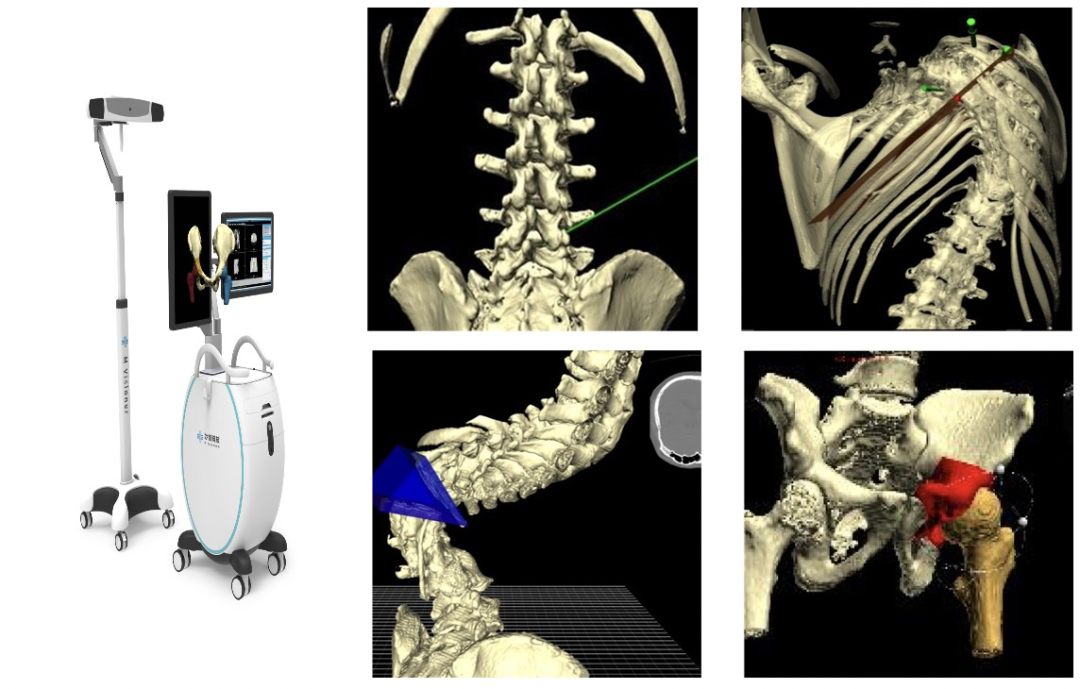

mNavigation手术导航系统则集合了术前规划功能,通过 VR医学图像渲染引擎和AI多模态融合,用虚拟现实场景帮助医生进行术前规划,10秒钟内完成CT及MR影像自动配准、人工智能分割。术中实现的毫米级实时手术器械定位及配准,还为医生提供全方位的智能化诊疗服务。目前,该产品已获得国际 CE注册证书,并在国内获得 NMPA临床测试许可。

mNavigation虚拟现实手术导航

为帮助医生更加准确地诊断患者病情,妙智科技研发的 mVR虚拟现实手术规划系统能够根据病人病变部位扫描的横断面图像,进行冠状位、矢状位的二维重建与三维重建,多角度、直观观察病情,使病情的诊断更加准确。

另外,医生可在全立体VR空间内重建为患者进行术前精准规划,包括穿刺、椎弓根置钉、严重畸形矫正、髋关节截骨、髋置换等眷柱外科及关节外科手术等。系统通过人工智能算法进行解剖标志自动识别及输出相关的手术参数的测量,辅助医生更快速、准确地完成手术,提高手术成功率,减少医源性损伤和手术并发症。

mVR虚拟现实手术规划系统